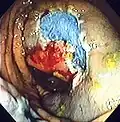

-

Polyp is identified. -

A sterile solution is injected under the polyp to lift it away from deeper tissues. -

A portion of the polyp is now removed. -

The polyp is fully removed.